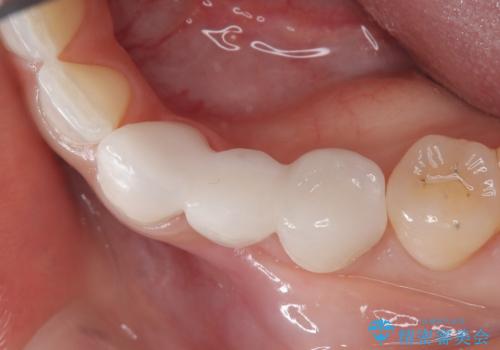

欠損歯をブリッジにて補綴

- 左下の歯が生まれつき無かった患者様です。

矯正治療にてスペースを一箇所に集めてからオールセラミックブリッジにて補綴治療を行いました。

今回は、患者様の希望もありインプラントではなくブリッジにて修復しています。